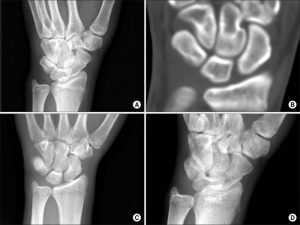

Диагноз

Первая помощь Хирург сможет диагностировать перелом запястья при первичном осмотре. Поврежденные кости находятся в определенном, им не свойственном положении. Для выявления полной клинической картины специалист выясняет жалобы и проводит полную диагностику. Определить совокупность повреждений позволяет рентгенография. Если этот метод недостаточно информативен, назначают КТ или ядерно-резонансную томографию.

При переломе руки по разгибательному типу запястья больной ходит в гипсе до полутора месяцев. При травме Смита гипс носят до 8 недель. Рука заживает дольше при множественных осколках. Если через месяц после травмы перелом не сросся, то повторно накладывают иммобилизирующую повязку.